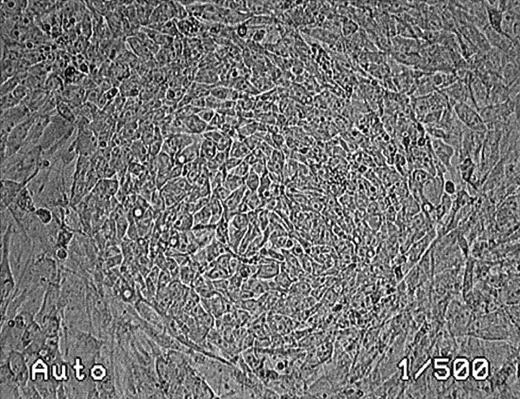

The R366.4 rhesus monkey ES cell line was described previously.12 Cells were maintained in the undifferentiated state by coculture with irradiated murine embryonic feeder cells (Figure 1). ES and feeder cells were cultured in gelatin-coated flasks in Dulbecco modified Eagle medium (Gibco, St Louis, MO) supplemented with 15% fetal-calf serum (FCS; Hyclone, Logan, UT), 1 mM glutamine, 1 × 10−4 M 2-mercaptoethanol, and 2% minimum essential medium amino acids solution (Gibco).

Phase-contrast photomicrograph of an undifferentiated rhesus monkey ES cell colony (magnification, ×100).